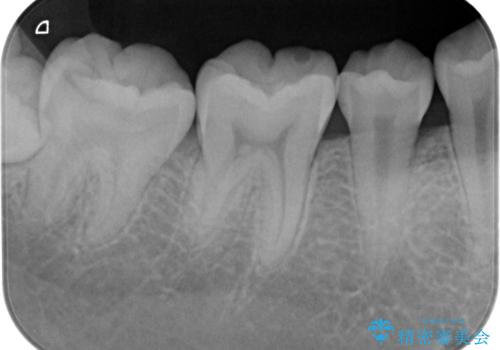

- 検査の結果虫歯が見つかった患者様です。

親知らずを抜歯してから虫歯を除去した後、ゴールドの詰め物で修復します。